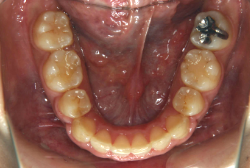

「左奥歯でものが噛めない」という主訴で来院したケースです。診断の結果、基本的には「叢生」という隙間が足りないと言うことが原因の凸凹症例でしたが、左下の乳歯が高校生になってもまだ残存している状態で、そのせいで噛み合わせが極端に悪くなっていました。

検査の結果、乳歯の下には後継ぎの永久歯が先天的に欠如していました。配列の凸凹が厳しく非抜歯で矯正することは難しく、仮に無理をして非抜歯治療をしても後々「後戻り」が懸念されることから、このような症例の場合は通常、上下顎左右第一小臼歯を抜歯させていただくのですが、左下は乳歯を抜歯して、第一小臼歯は残すことにしました。これで結果として、小臼歯部を上下左右で一つずつ減らしたのと同じ状況になります。治療後は歯並びが綺麗になっただけでなく、噛み合わせ的にも正しい状態が確立しています。

このように、先天的に永久歯が足りないという症例は最近増えています。親知らずはなくても特に問題になりませんが、その他の歯が足りないと言うのは審美的にも機能的にも重大な障害となります。しかし、矯正治療を正しく行えば、結果として歯がすべてあった場合と全く同じ仕上げにすることも可能です。